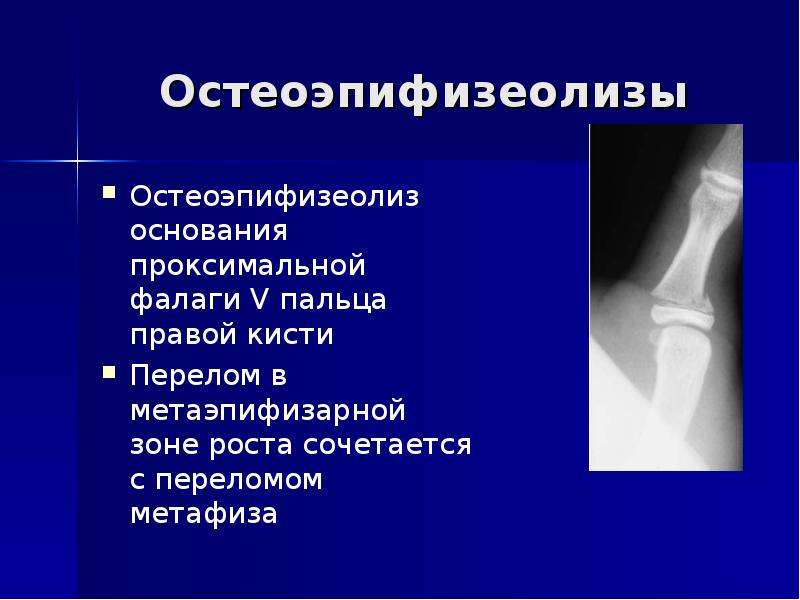

25. Остеоэпифизеолизы

Остеоэпифизеолиз

основания

проксимальной фалаги

V пальца правой кисти

Перелом в

метаэпифизарной зоне

роста сочетается с

переломом метафиза

Остеоэпифизеолизы

Остеоэпифизеолиз основания проксимальной фалаги V пальца правой кисти

Перелом в метаэпифизарной зоне роста сочетается с переломом метафиза